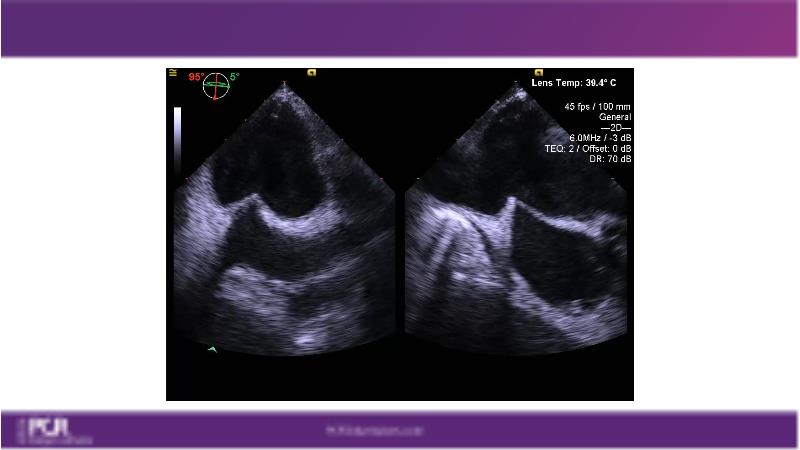

Watch this session to get an overview of a new TEER device, follow the step-by-step procedure related to initial experiences with this device for a Japanese patient with degenerative mitral regurgitation, learn about the latest data from RCT and registries, and follow discussions of challenging TEER cases!

- To learn procedural step-by-step of novel device